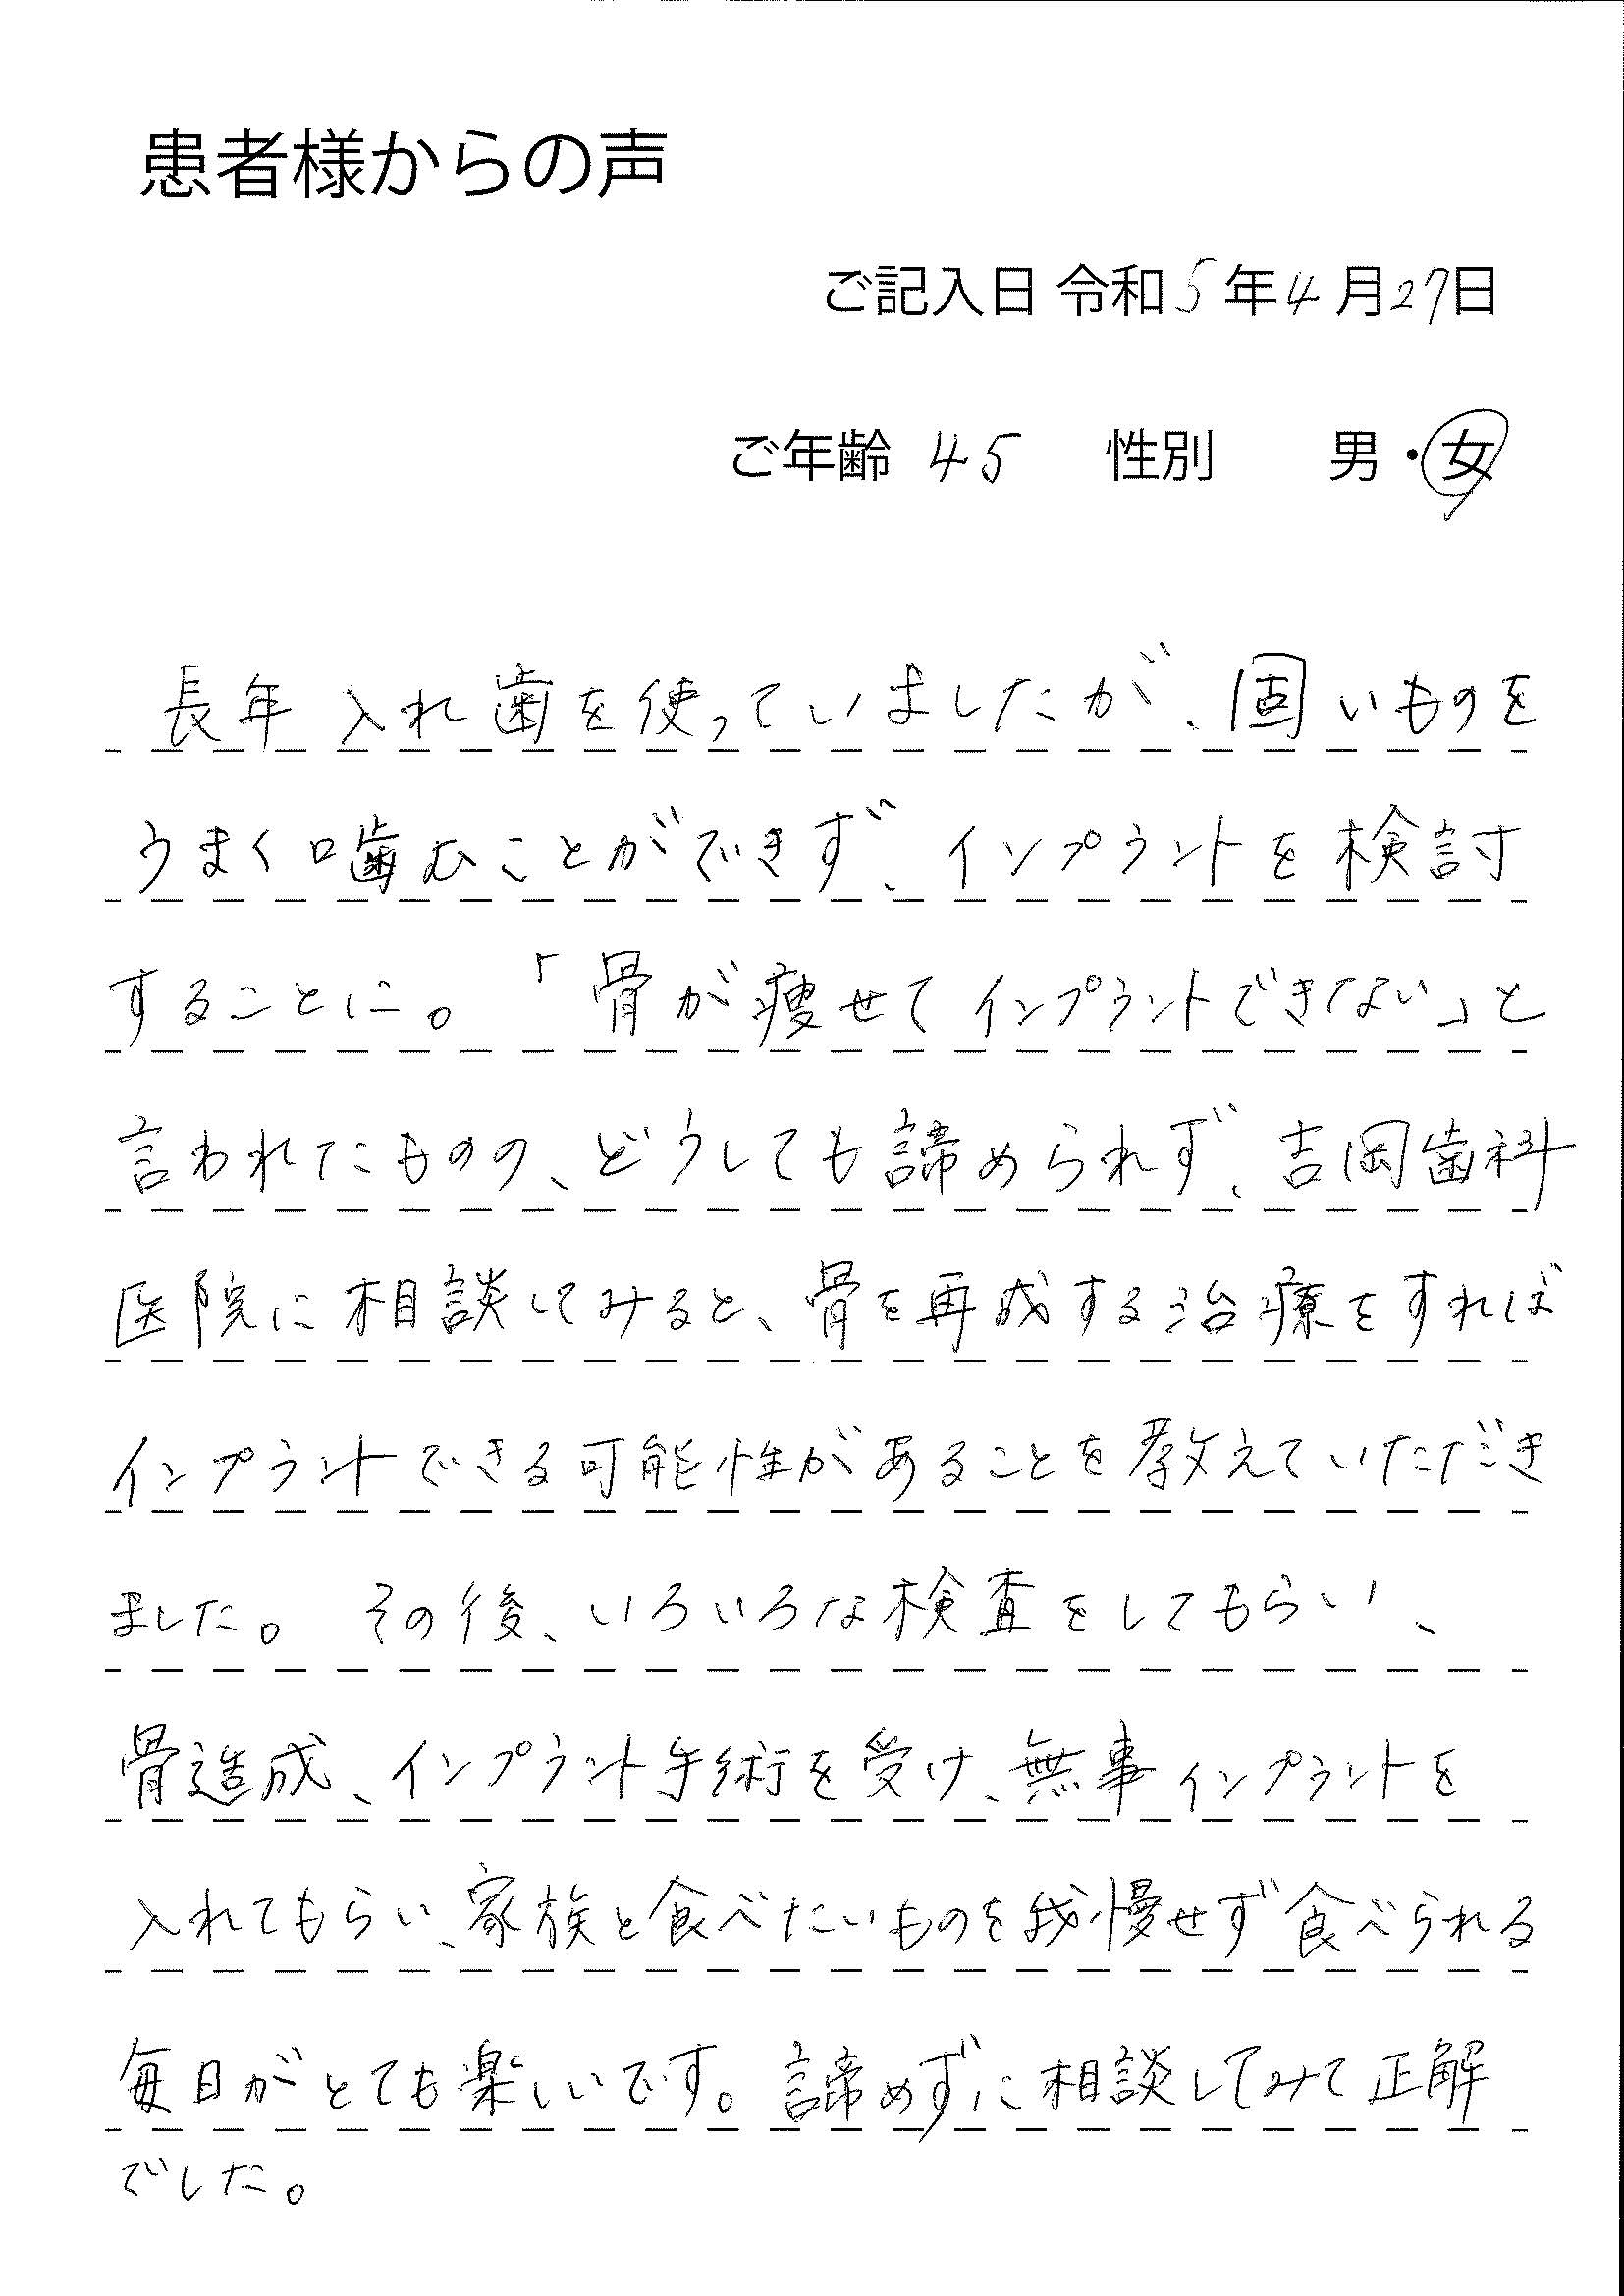

骨の量が原因で治療を断られてしまった方でも、正確な診断と高度な技術による骨造成を行うことでインプラント治療を受けられる可能性があります。

当院は骨造成処置に対応

骨造成は、難易度が高く治療技術と経験が問われるため、実際に高い成功率を持って治療を行える歯科医師はごくわずかです。

中部地方の中核インプラント施設として、インプラントの難しい症例に対応してきました。各地の歯科医療機関様よりご依頼を受けて、難しい骨造成症例の解決に取り組んでおります。